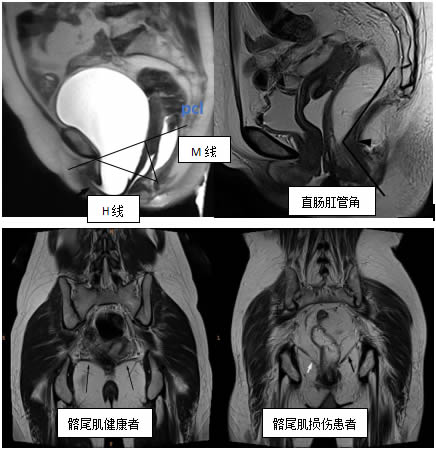

評估靜息態及動態時的直腸肛管角、H線、M線等,雙側髂骨尾骨肌、恥骨尾骨肌(jī)、恥骨直腸肌(jī)、提肌平麵等盆底(dǐ)支持(chí)結構,借助PCL輔助線(xiàn)診斷盆底器官的脫垂等情況。